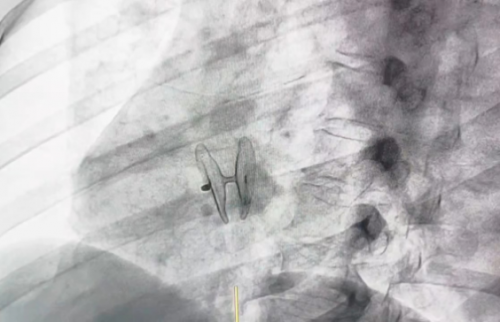

患者为30岁女性,因“言语含糊、左侧肢体乏力10余天,偏头痛10余年”入院,入院完善检查后提示有腔隙脑梗,超声检查示房间隔膨出瘤,Valsalva动作下心房水平右向左分流3级。董念国教授团队与当地心脏科、神经科、超声科等医生共同协作,经过全面而细致的评估,明确诊断为卵圆孔未闭。在充分考虑患者及其家属的意愿,并致力于实现患者利益最大化的基础上,决定采用D-shufo 卵圆孔未闭封堵器对患者进行人道主义救治。

整个手术过程流畅高效,封堵器释放位置精准,与周围组织贴合紧密。术后复查超声显示,封堵器未对二尖瓣、三尖瓣组织产生任何影响,且无残余分流现象。患者在术后次日即顺利出院,至今随访结果显示,患者头痛、头晕等症状未再复发,且无卒中复发的迹象。